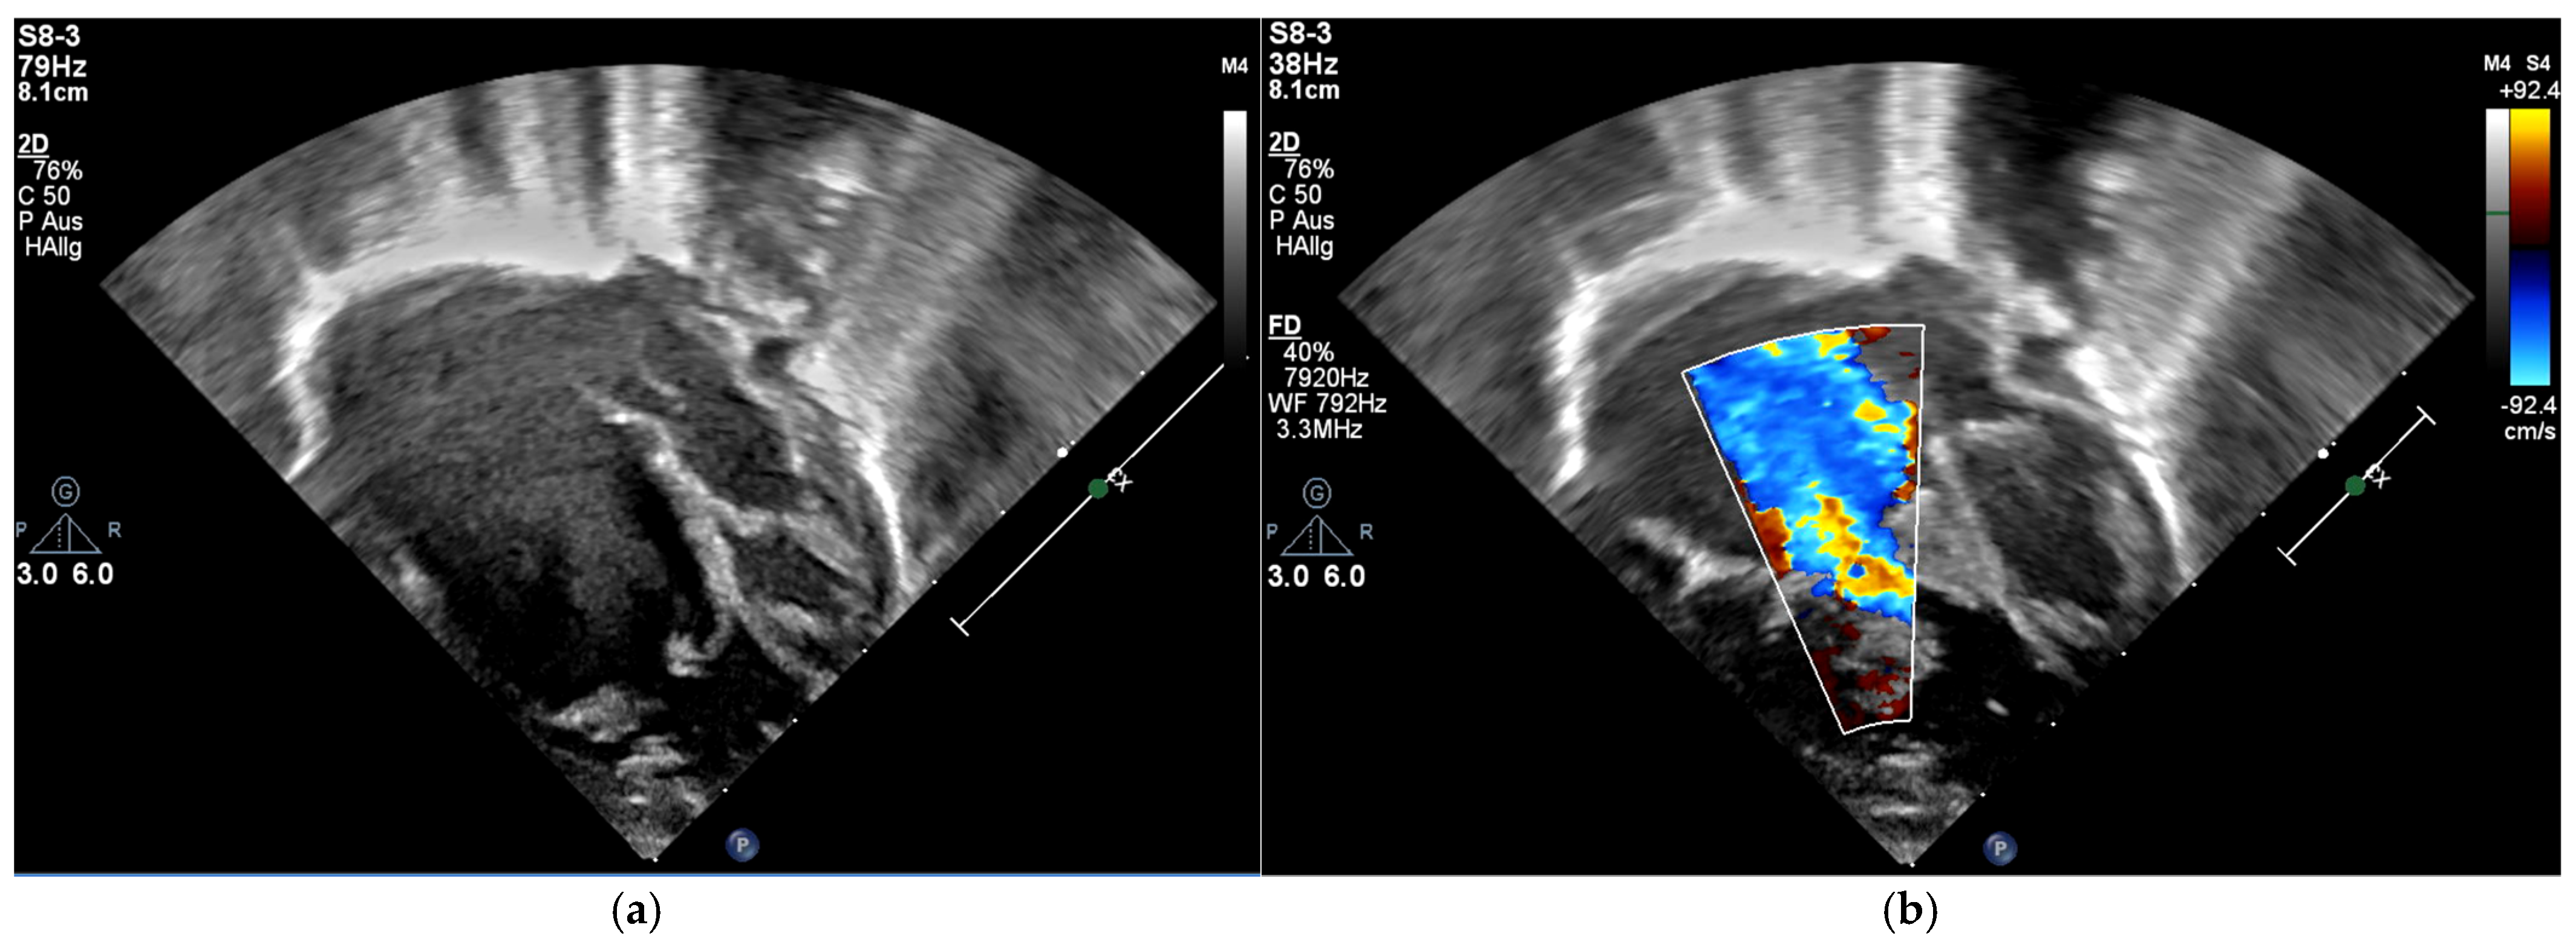

Figure 2. Echocardiography, four-chamber view; (a) the apical displacement of the tricuspid valve; (b) color-flow Doppler showing severe tricuspid regurgitation; immediately postpartum.

The patient was born late-preterm by cesarean section (36 + 3 weeks’ gestation, birth weight 2400 g, APGAR 6/9/9, umbilical cord pH = 7.38) with prenatally diagnosed EA; we started immediate, uncomplicated primary care with CPAP respiratory support, umbilical vein catheter and prostaglandin E (PGE) infusion for ductus-dependent lung perfusion. With stable hemodynamics, the neonate was transferred to our pediatric cardiac intensive care unit (pCICU). At admission, the patient exhibited independent feeding ability, a heart rate of 150 bpm, pre- and postductal oxygen saturation was >85%, and additional oxygen was required until the third day of life. ECG showed sinus rhythm with P-dextroatriale, QRS of approx. 80 ms, and no arrhythmia. On the second day postpartum, Troponin I and proBNP were measured as 9 pg/mL and 27,065 ng/L, respectively. Mild signs of heart failure were treated with diuretics. Echocardiography confirmed severe EA, consistent with Carpentier type C, with RA/(RV + LA + LV) > 1 (RA = right atrium; LA = left atrium), ASD type II of 10 mm, and the prolapse of the anterior leaflet of the TV into the RVOT leading to severe insufficiency with a coaptation defect and a V. contracta of 1.2 cm. Additionally, membranous pulmonary atresia with preserved confluence was found. The pulmonary arteries (PAs) were hypoplastic, with left PA (LPA) = 2.7 mm (z = −2.3) and right PA (RPA) = 3.2 mm (z = −1.7). The left-sided heart segments did not show any malformation, insufficiency, or stenosis, and their function was deemed to be satisfactory (fractional shortening (FS) = 22.6%; see Figure 1 and Figure 2, Supplementary Materials, Figure S1).